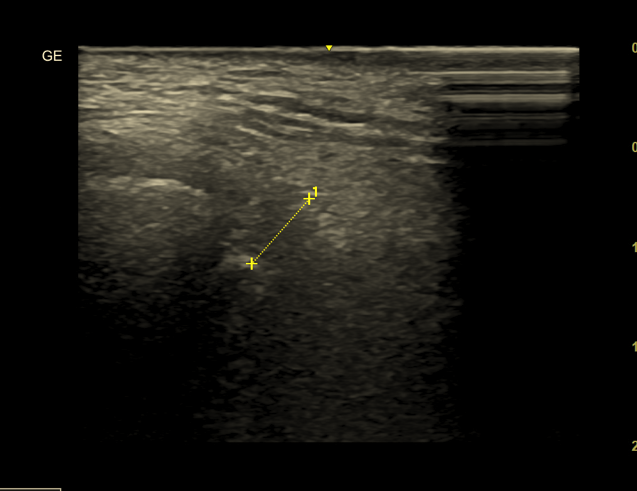

1. USG stawu skroniowo-żuchwowego a szumy uszne

Staw skroniowo-żuchwowy znajduje się bardzo blisko przewodu słuchowego. Jego patologie często powodują objawy imitujące choroby ucha.

Czy USG wykryje przyczynę szumów usznych w TMJ?

Tak – jeśli przyczyną jest:

• wysięk w jamie stawu

• stan zapalny

• pogrubienie torebki stawowej

USG szumy uszne w kontekście TMJ warto rozważyć, gdy:

• szum jest jednostronny

• pojawia się ból przed uchem

• występują trzaski przy otwieraniu ust

USG jest szybkim i nieinwazyjnym badaniem, które może potwierdzić obecność płynu w stawie.